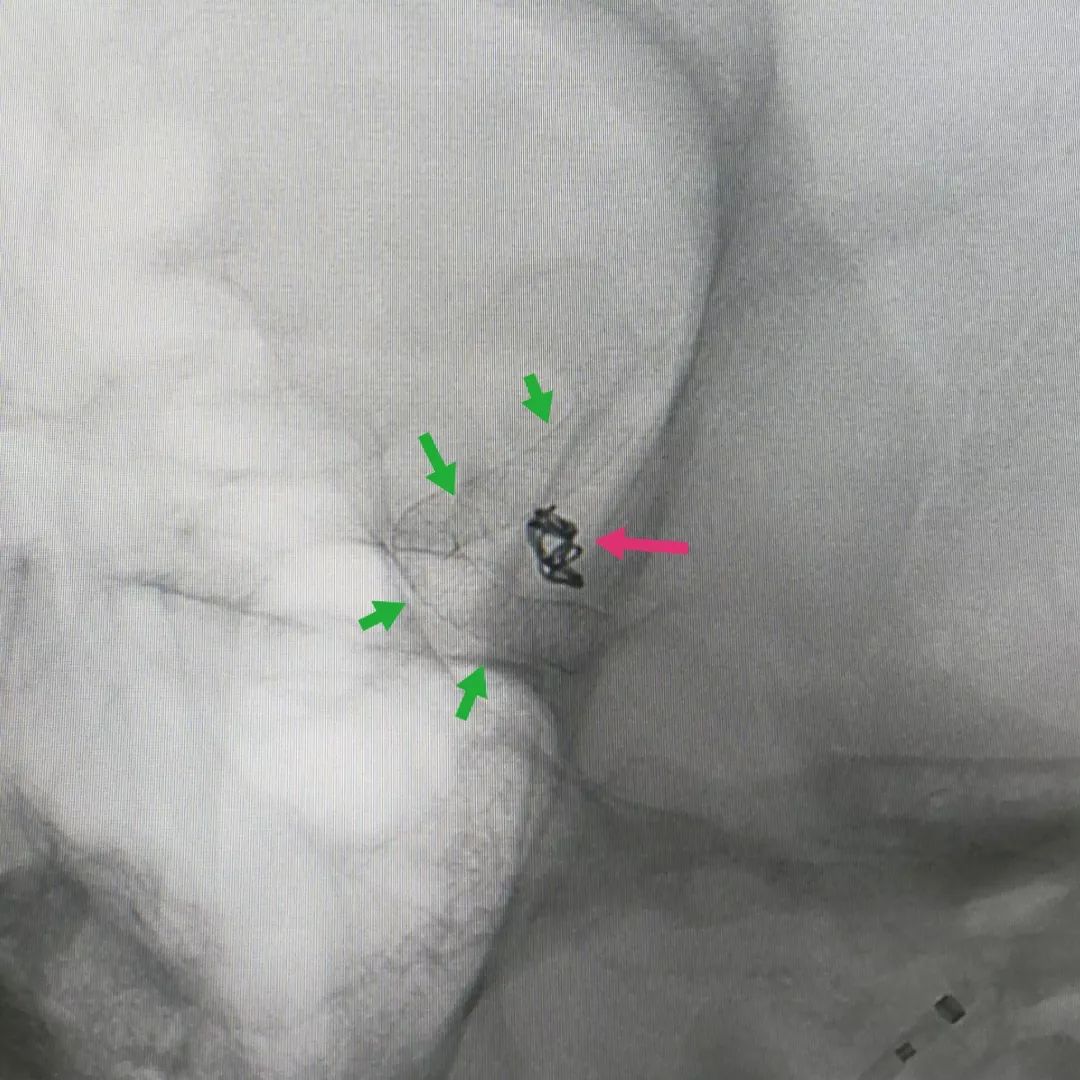

而且两个动脉瘤同时治疗难度和风险增加。所以我们采用了目前最先进的密网支架技术,既能保证重要血管通畅,又能彻底治愈动脉瘤。手术后可见支架完全贴合血管壁(下图绿色箭头)